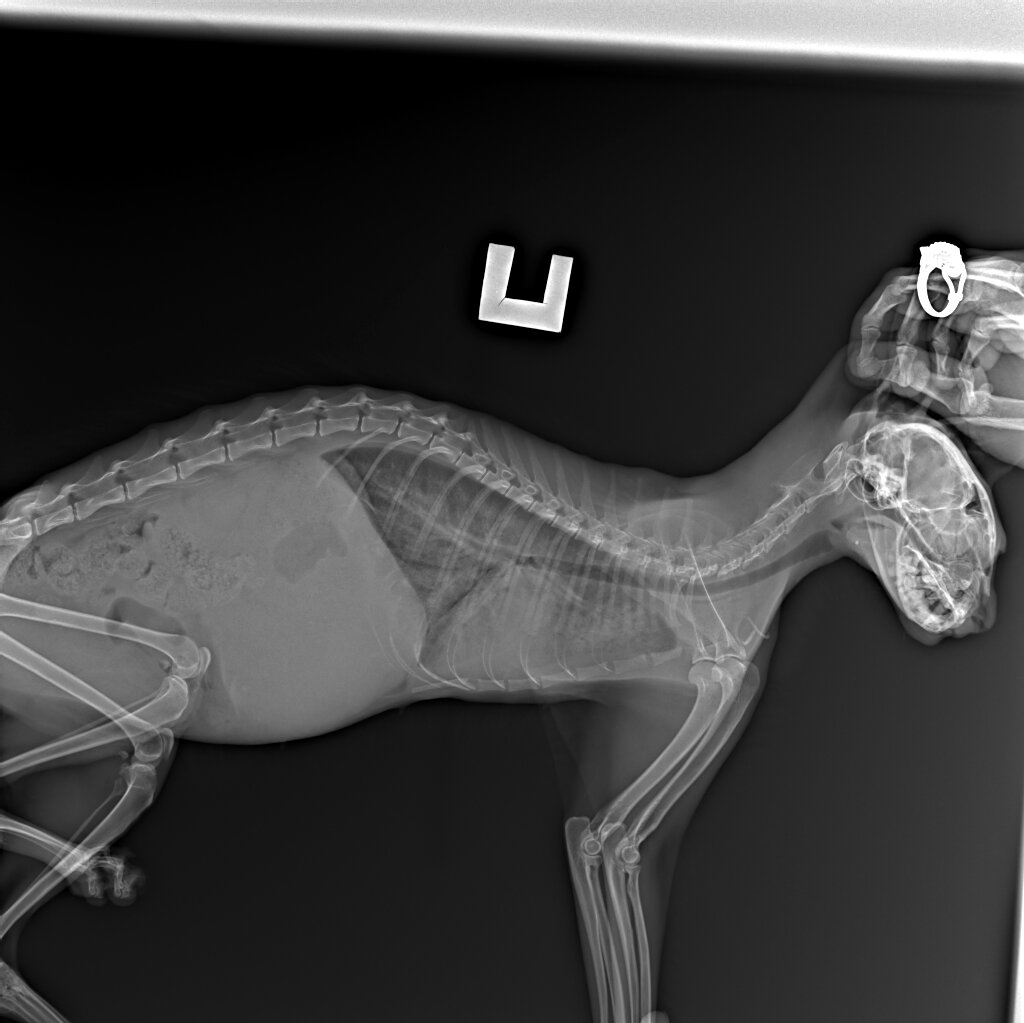

Фото автора. Рентген ЛюсИ.

Сделали рентген и, отёк лёгких, воспаление и жидкость.